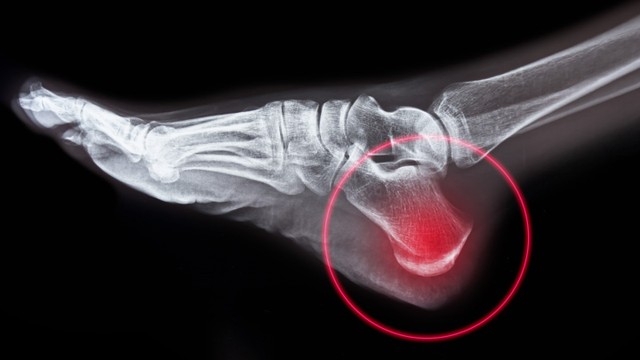

:format(webp)/vdxg2_73717ffaeb.jpeg)

Viêm đầu xương gót hay còn gọi bệnh Sever, là một trong những nguyên nhân phổ biến nhất gây đau gót chân ở trẻ đang lớn, đặc biệt là trẻ hoạt động thể chất nhiều. Đó là tình trạng viêm của đĩa tăng trưởng ở xương gót chân. Viêm đầu xương gót là do quá trình căng thẳng lặp đi lặp lại ở gót chân. Bệnh thường xảy ra nhất trong giai đoạn tăng trưởng nhanh, khi xương, cơ, gân và các cấu trúc đang thay đổi nhanh chóng.